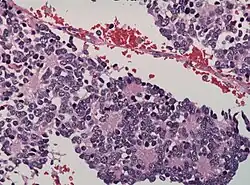

Dysgerminoma | Dysgerminoma characterized by uniform cells resembling primordial germ cells separated by fibrous septa with lymphocytes. | Category: Histopathology of ovarian dysgerminoma | Ovarian dysgerminoma |